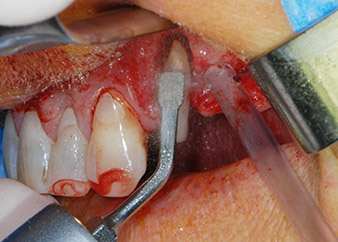

Въпреки това, ние се придържахме към първоначалния си план да запазим и двата зъба като абатмънти за временен мост по време на 6-месечната остеоинтеграция на имплантите. При повторна интервенция, ситуацията трябва да се преразгледа. Първо, в опит да се овладее ендо-перио проблема, останалата повърхност на зъба е внимателно обработена с пиезохирургично оборудване (Piezomed, W&H, използван с накрайник S1 под формата на шпатула, първоначално проектиран за ерозия на латералната синусна стена) (Фиг. 4).

периодонциум

Фиг. 4: За да се съхрани зъбът като временен абатмънт, периодонциумът е изпилен с пиезохирургично оборудване...

букален апекс на зъб 24

Фиг 5: ... и букалният апекс на зъб 24 е обработен със същия инструмент (апикоектомия).